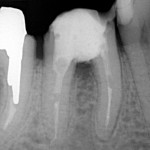

Poniżej zdjęcie rentgenowskie po zabiegu premolaryzacji. Widzimy już dwa oddzielne zęby.

Gojenie trwa około roku.

Jeśli zdjęcie rentgenowskie wykonane po roku pokazuje wygojoną kość a pacjent nie ma żadnych dolegliwośći, można przystąpić do odbudowy protetycznej.

Wykonuje się dwie mniejsze korony zamiast jednej, co umożliwia prawidłowe czyszczenie. Zęby wyglądają naturalnie i spełnieją swe funkcje.